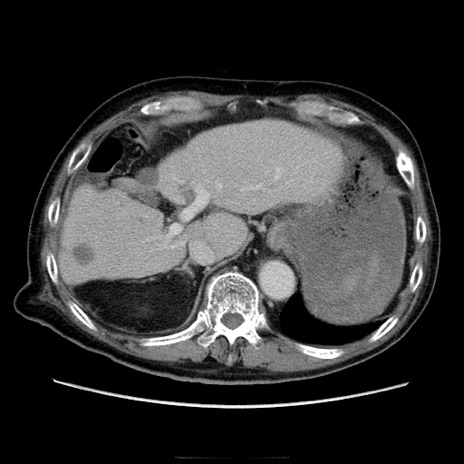

冠状断像

【症例】70歳代男性

【主訴】腹痛

【現病歴】肝硬変・肝細胞癌にてかかりつけの方。約9時間前に食後より腹痛出現。症状が徐々に増悪し、嘔吐出現したため来院。

【既往歴】肝硬変、肝細胞癌(RFA、TACE後)

【身体所見】意識清明、表情苦悶様、BT 36℃、BP 129/78mmHg、P 88bpm、SpO2 97%(RA)、右上腹部から心窩部にかけて圧痛あり、反跳痛なし、筋性防御あり。

【データ】WBC 5800、CRP 0.16